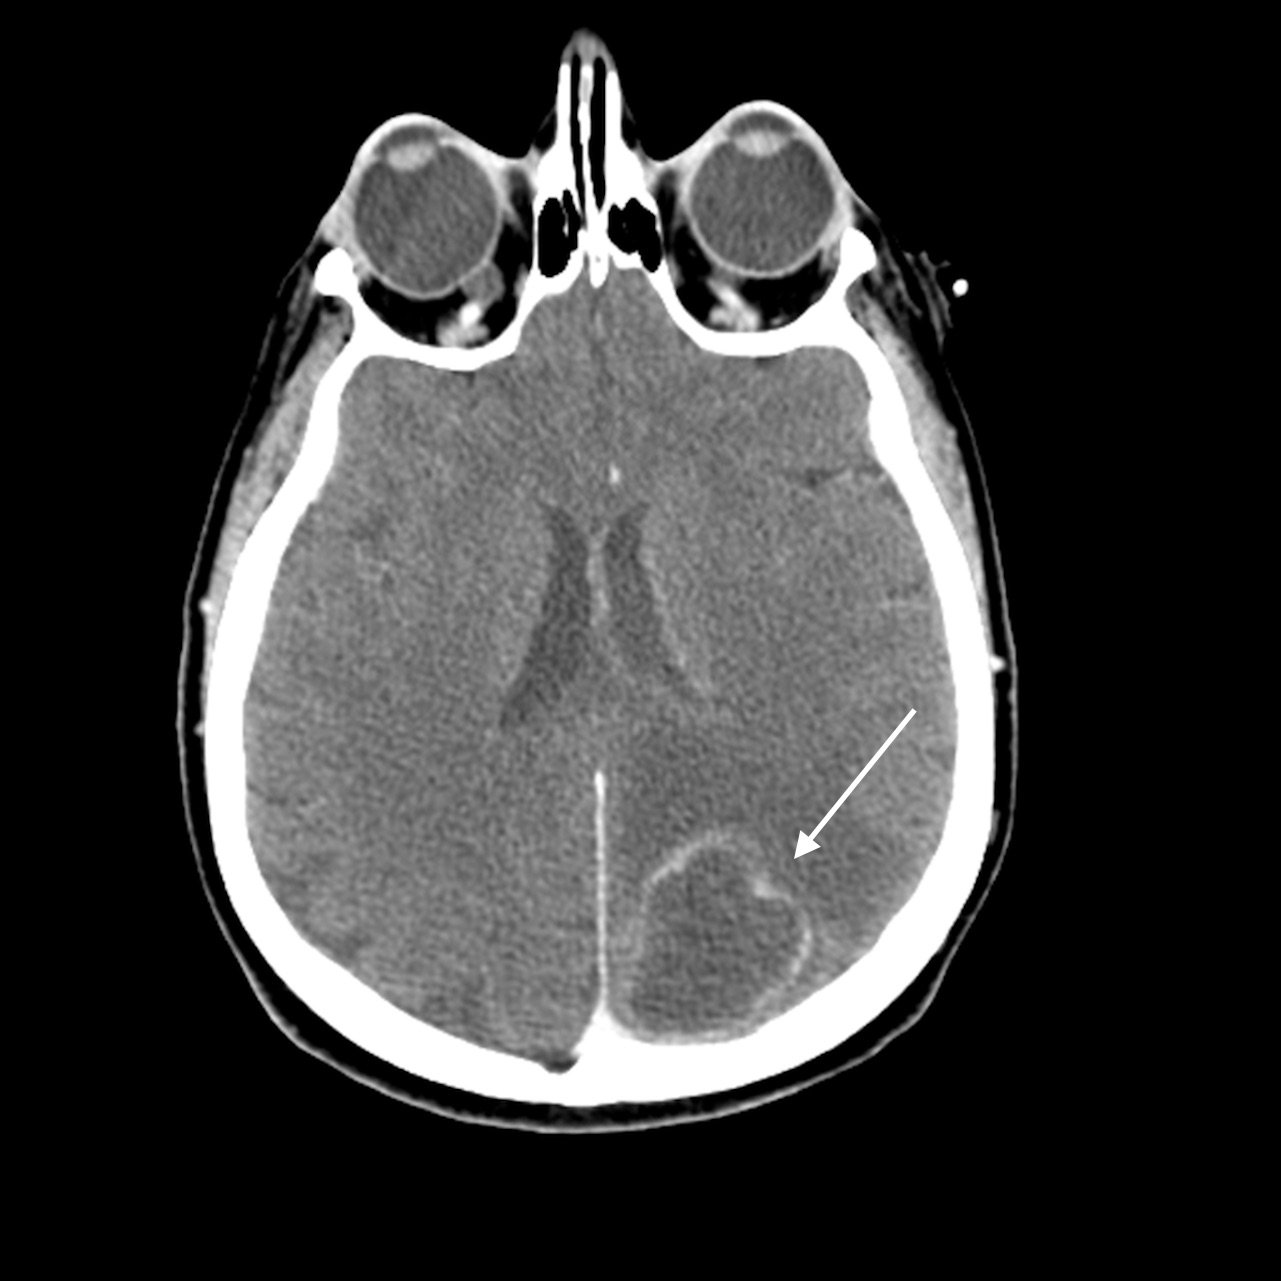

A 64-year-old woman with a remote history of breast cancer presented to the emergency department with one day of worsening right-sided weakness and headaches. She had been seen two weeks prior for similar symptoms and underwent unenhanced brain computed tomography (CT), which revealed a left parietal mass suspected to represent new metastatic disease. The patient presented on this visit not only with weakness of her right upper and lower extremity, but was found to be febrile, tachycardic and exhibiting lethargy. Peripheral white blood cell count (WBC) was 27.1 (x103/mm3). Given her rapidly declining clinical course and expected time to complete magnetic resonance imaging (MRI) of the brain, the decision was made to first perform an emergent contrast-enhanced brain CT to further evaluate the mass. The contrast-enhanced brain CT revealed a large rim-enhancing left parietal lesion.

A non-contrast CT (Figure 1) revealed a large hypoattenuating left parietal lesion. When the CT was enhanced with intravenous contrast (Figure 2), the same lesion showed peripheral rim enhancement, suggestive of a brain abscess.

Classic CT features favoring an abscess include a continuous thin rim of peripheral enhancement and thinning along the medial wall.6 However, these are nonspecific and frequently difficult to differentiate from high-grade neoplasms, metastases, infarcts, or hematomas. MRI with gadolinium is therefore significantly more sensitive and specific for diagnosing and differentiating a brain abscess from primary or metastatic cancer. Prospective studies report a sensitivity and specificity of about 96% for MRI when combined with diffusion-weighted imaging.1,5